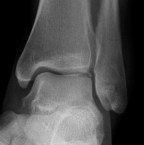

Ankle arthroscopy can be helpful for patients who have damage to the cartilage of the ankle joint. Typically sustained after an ankle sprain, some people who have continued pain may have a small piece of bone and cartilage that is loose inside the ankle joint.

Ankle arthroscopy can be used to remove the loose fragment, and perform surgery to help stimulate the growth of fibrocartilage in the defect. This is done through two small incisions at the front of the ankle. The surgery is very safe, with a very low risk of infection. The main risk is to small sensory nerves around the ankle.